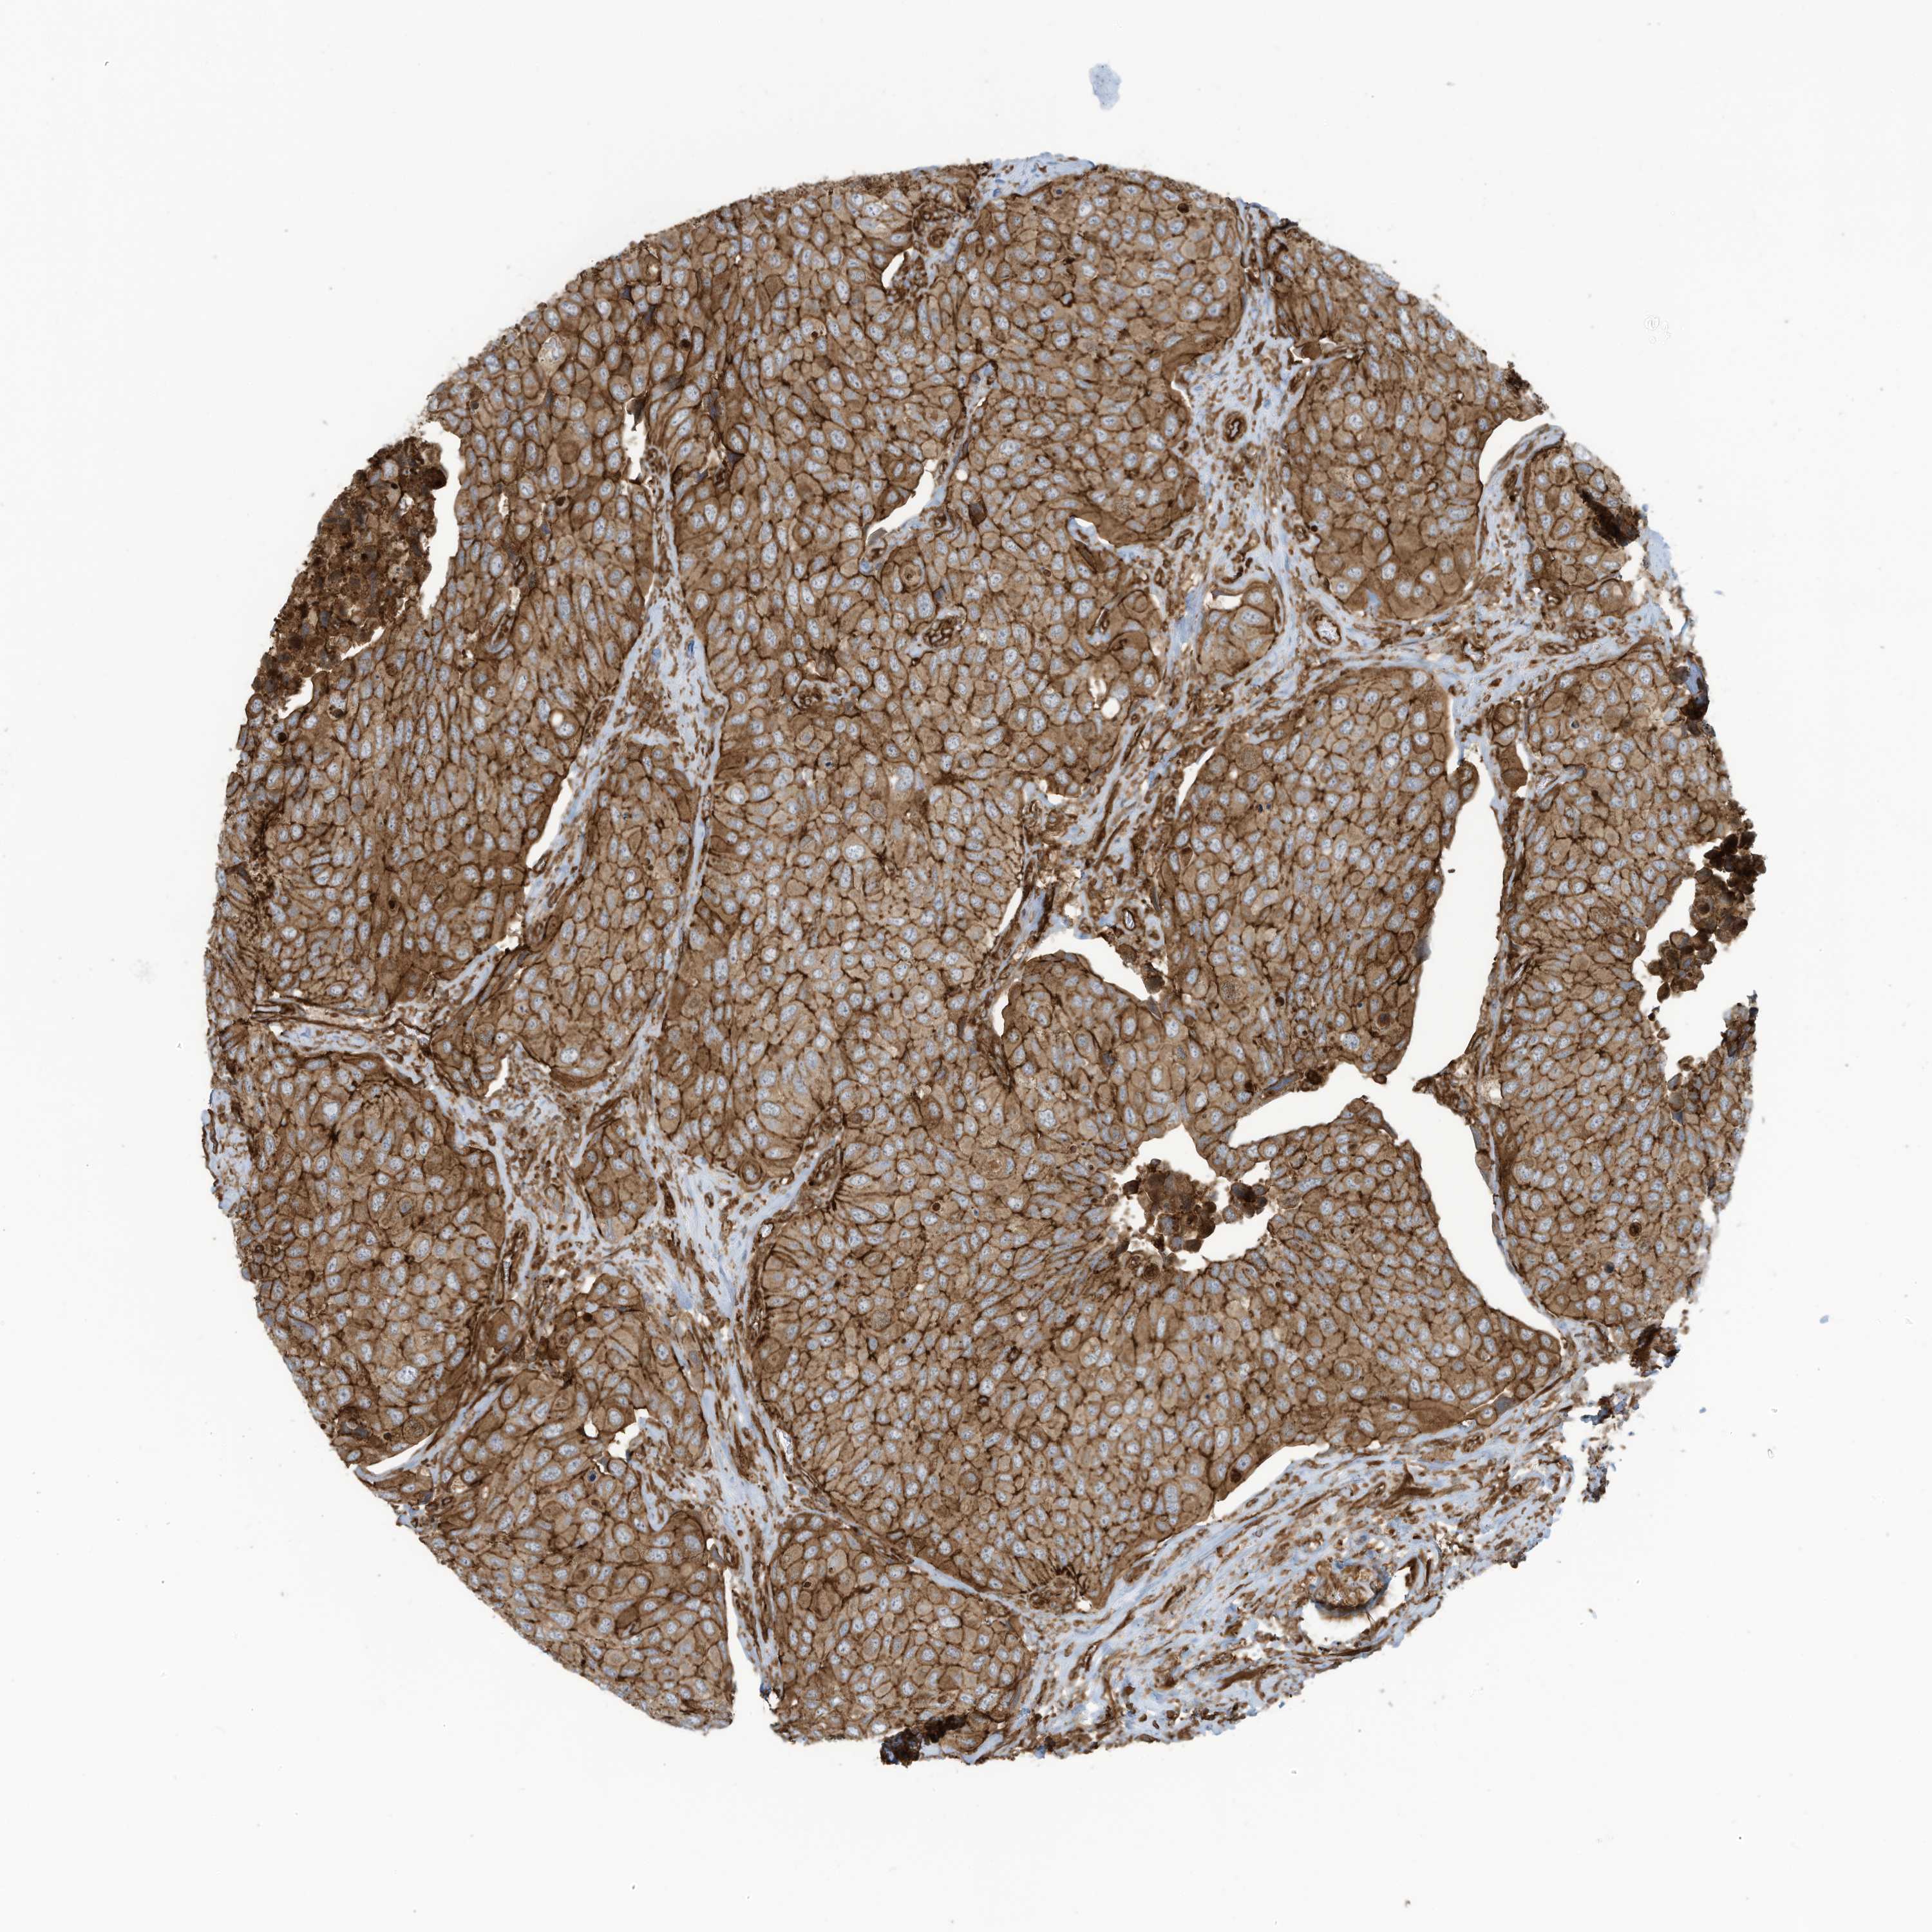

UROTHELIAL CANCER - Protein expressioni

A mouse-over function shows sample information and annotation data. Click on an image to view it in a full screen mode. Samples can be filtered based on level of antibody staining by selecting one or several of the following categories: high, medium, low and not detected. The assay and annotation is described here.

Note that samples used for immunohistochemistry by the Human Protein Atlas do not correspond to samples in the TCGA dataset.

Antibody stainingi

Antibody staining in the annotated cell types in the current human tissue is reported as not detected, low, medium, or high, based on conventional immunohistochemistry profiling in selected tissues. This score is based on the combination of the staining intensity and fraction of stained cells.

Each image is clickable and will lead to virtual microscopy that enables deeper exploration of all samples and also displays staining intensity scores, fraction scores and subcellular localization as well as patient and tissue information for each sample.

Antibody HPA035121

Antibody HPA035122

Staining

High

Medium

Low

Not detected

Intensity

Strong

Moderate

Weak

Negative

Quantity

>75%

75%-25%

<25%

None

Location

Nuclear

Cytoplasmic/membranous

Cytoplasmic/membranous,nuclear

Urothelial carcinoma, High grade

Urothelial carcinoma, Low grade